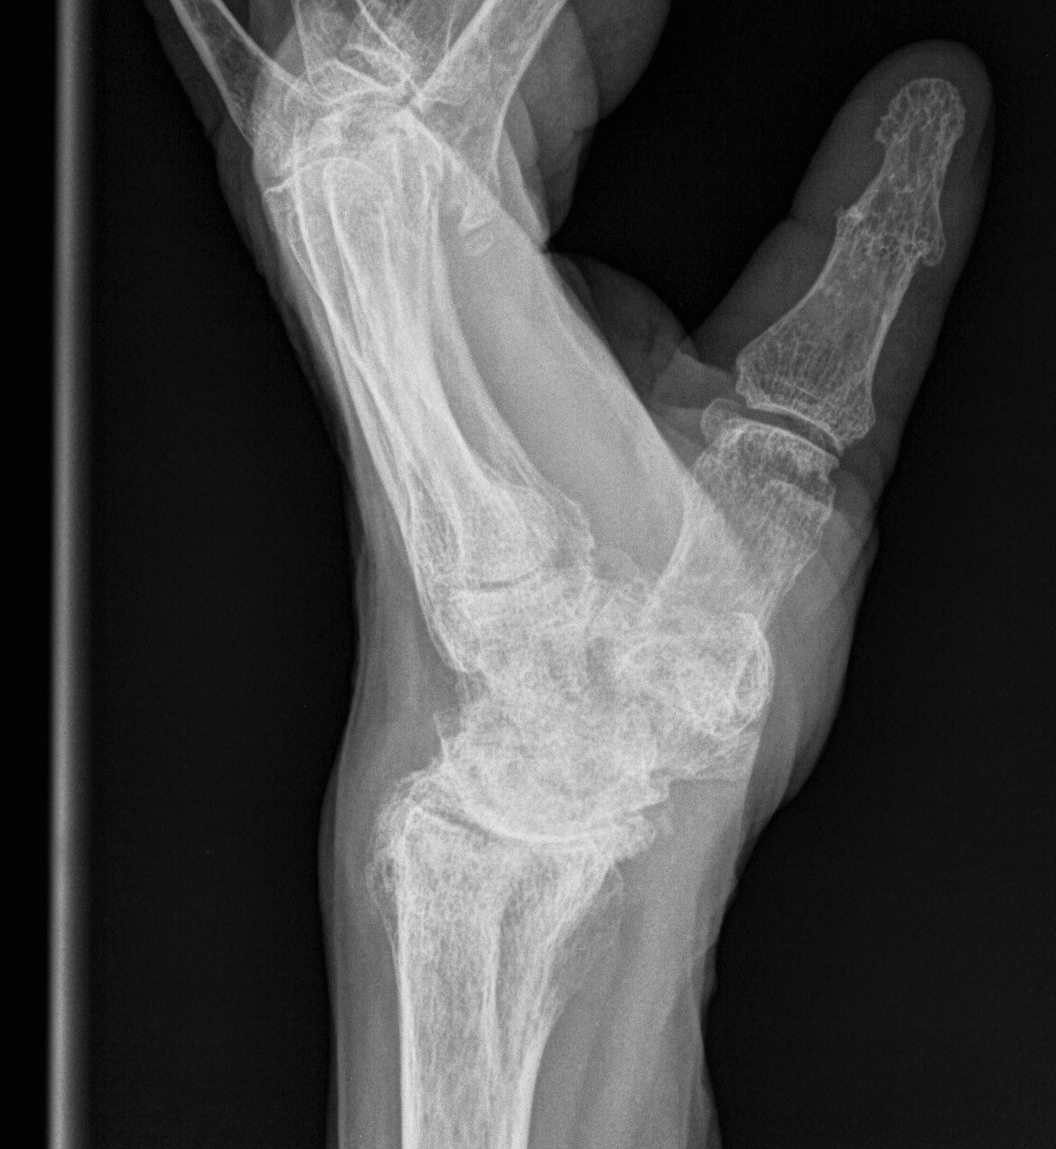

Xray